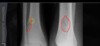

What is seen here in regards to density? (left is abnormal)

Permeative/Motheaten